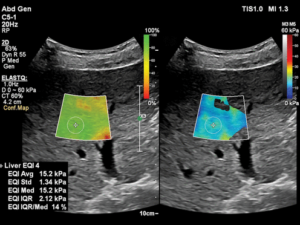

Liver elastography uses ultrasound or MRI-based technology to send gentle vibrations into the liver tissue. The machine then measures how quickly these waves pass through the liver:

The results are displayed as a color-coded map or numerical score, helping your doctor determine the extent of liver stiffness.

Interpreting the Results

The results are expressed in kilopascals (kPa) or as a fibrosis score (F0–F4):

F0–F1: Normal to mild fibrosis

F2–F3: Moderate fibrosis

F4: Advanced fibrosis or cirrhosis

Your doctor will review these findings along with other clinical data to form a complete diagnosis and treatment plan.